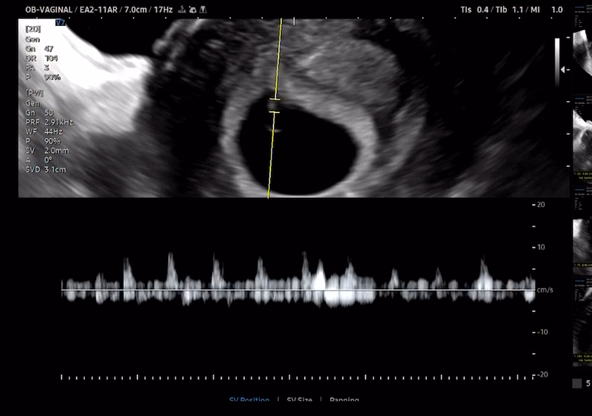

아기 심장 소리 들어보실래요?

의사 선생님은 지금 아이의 심장 소리를 들을 수 있다고 하셨다.

0.5cm 되는... 아직 세포라고 생각했는데 심장이 뛰다니.

진짜 멍하면서도 기분이 너무너무 이상했다.

오랑이는 눈물을 흘렸다.

우리의 아이가 생긴다는 것이 이런 기분이었을까.

정말 잊을 수 없는 생애 경험해 보지 못한 순간이었다.